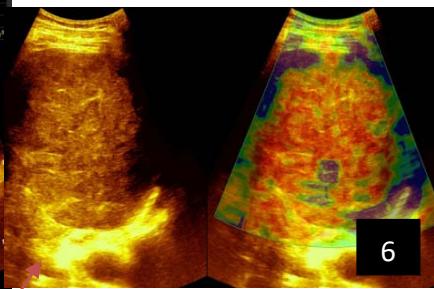

Iconography 1: 54-year-old patient with an intra-splenicsolid mass, anatomopathologically compatible with lymphoma: images 1 and 2: right pleurisy of moderateabundance, image3: celiacadenopathy, image 4: free ascites of moderateabundance, images 5 and 6: intra-splenicsolid mass of around $1418.16\mathrm{ml}$ in B mode and elastographyshowing areas of tumourrigidity, images 7-10: oblique linear images, showingbiopsy gun tracks.

Iconography B: 1 to 4: ultrasound images in mode B showing a large size, 5: ultrasound image in mode B showingsolidhyperechogenic nodules under the capsulorhexis, 6 to 10: ultrasound images in mode B showinglinearhyperechogenic images without overlay in relation to the trajectories of the aiguilles of biopsy.